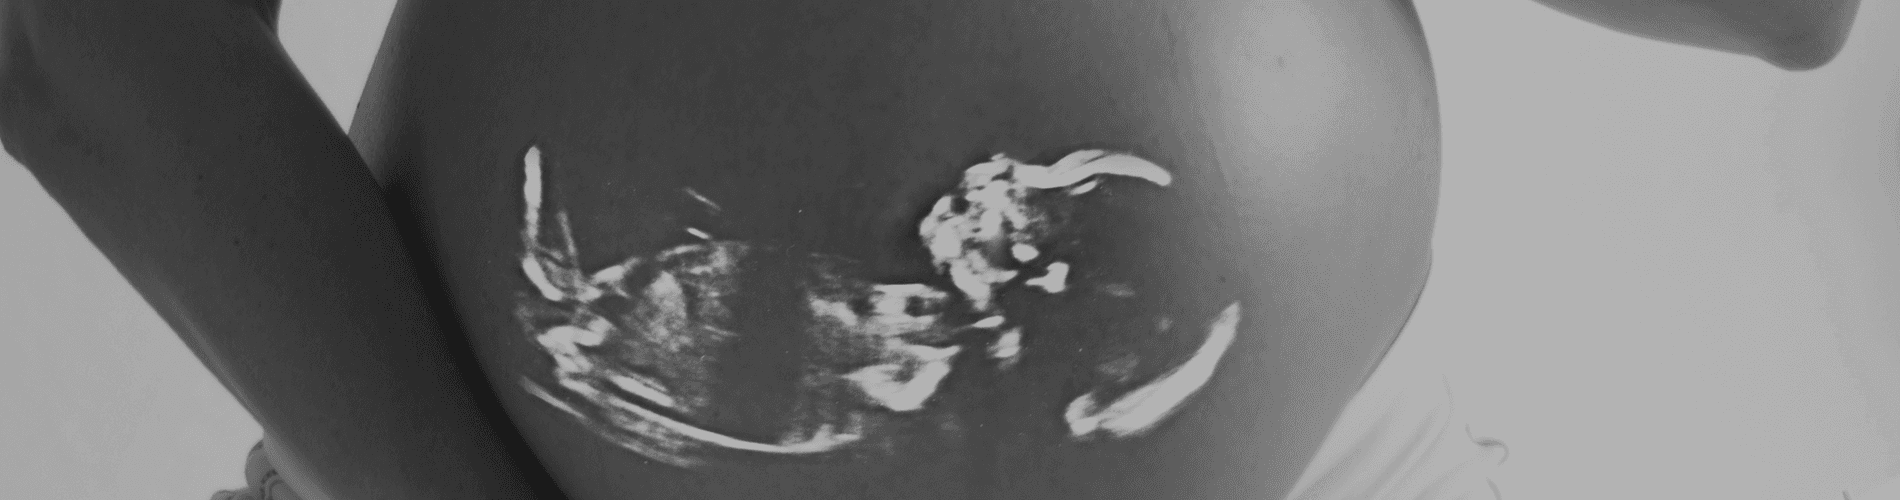

الإهمال الطبي في علاج الأطفال الخدج

بسبب التطور العلمي في هذا المجال، من الممكن اليوم علاج والحفاظ على حياة أطفال ولدوا في مراحل مبكرة جداً من الحمل، بحيث لا يمكن قبول الادعاء بشكل شامل بأن المخاطر التي يتعرض لها هؤلاء الأطفال هي ظاهرة لا مفر منها بسبب عمرهم وحالتهم الهشة.